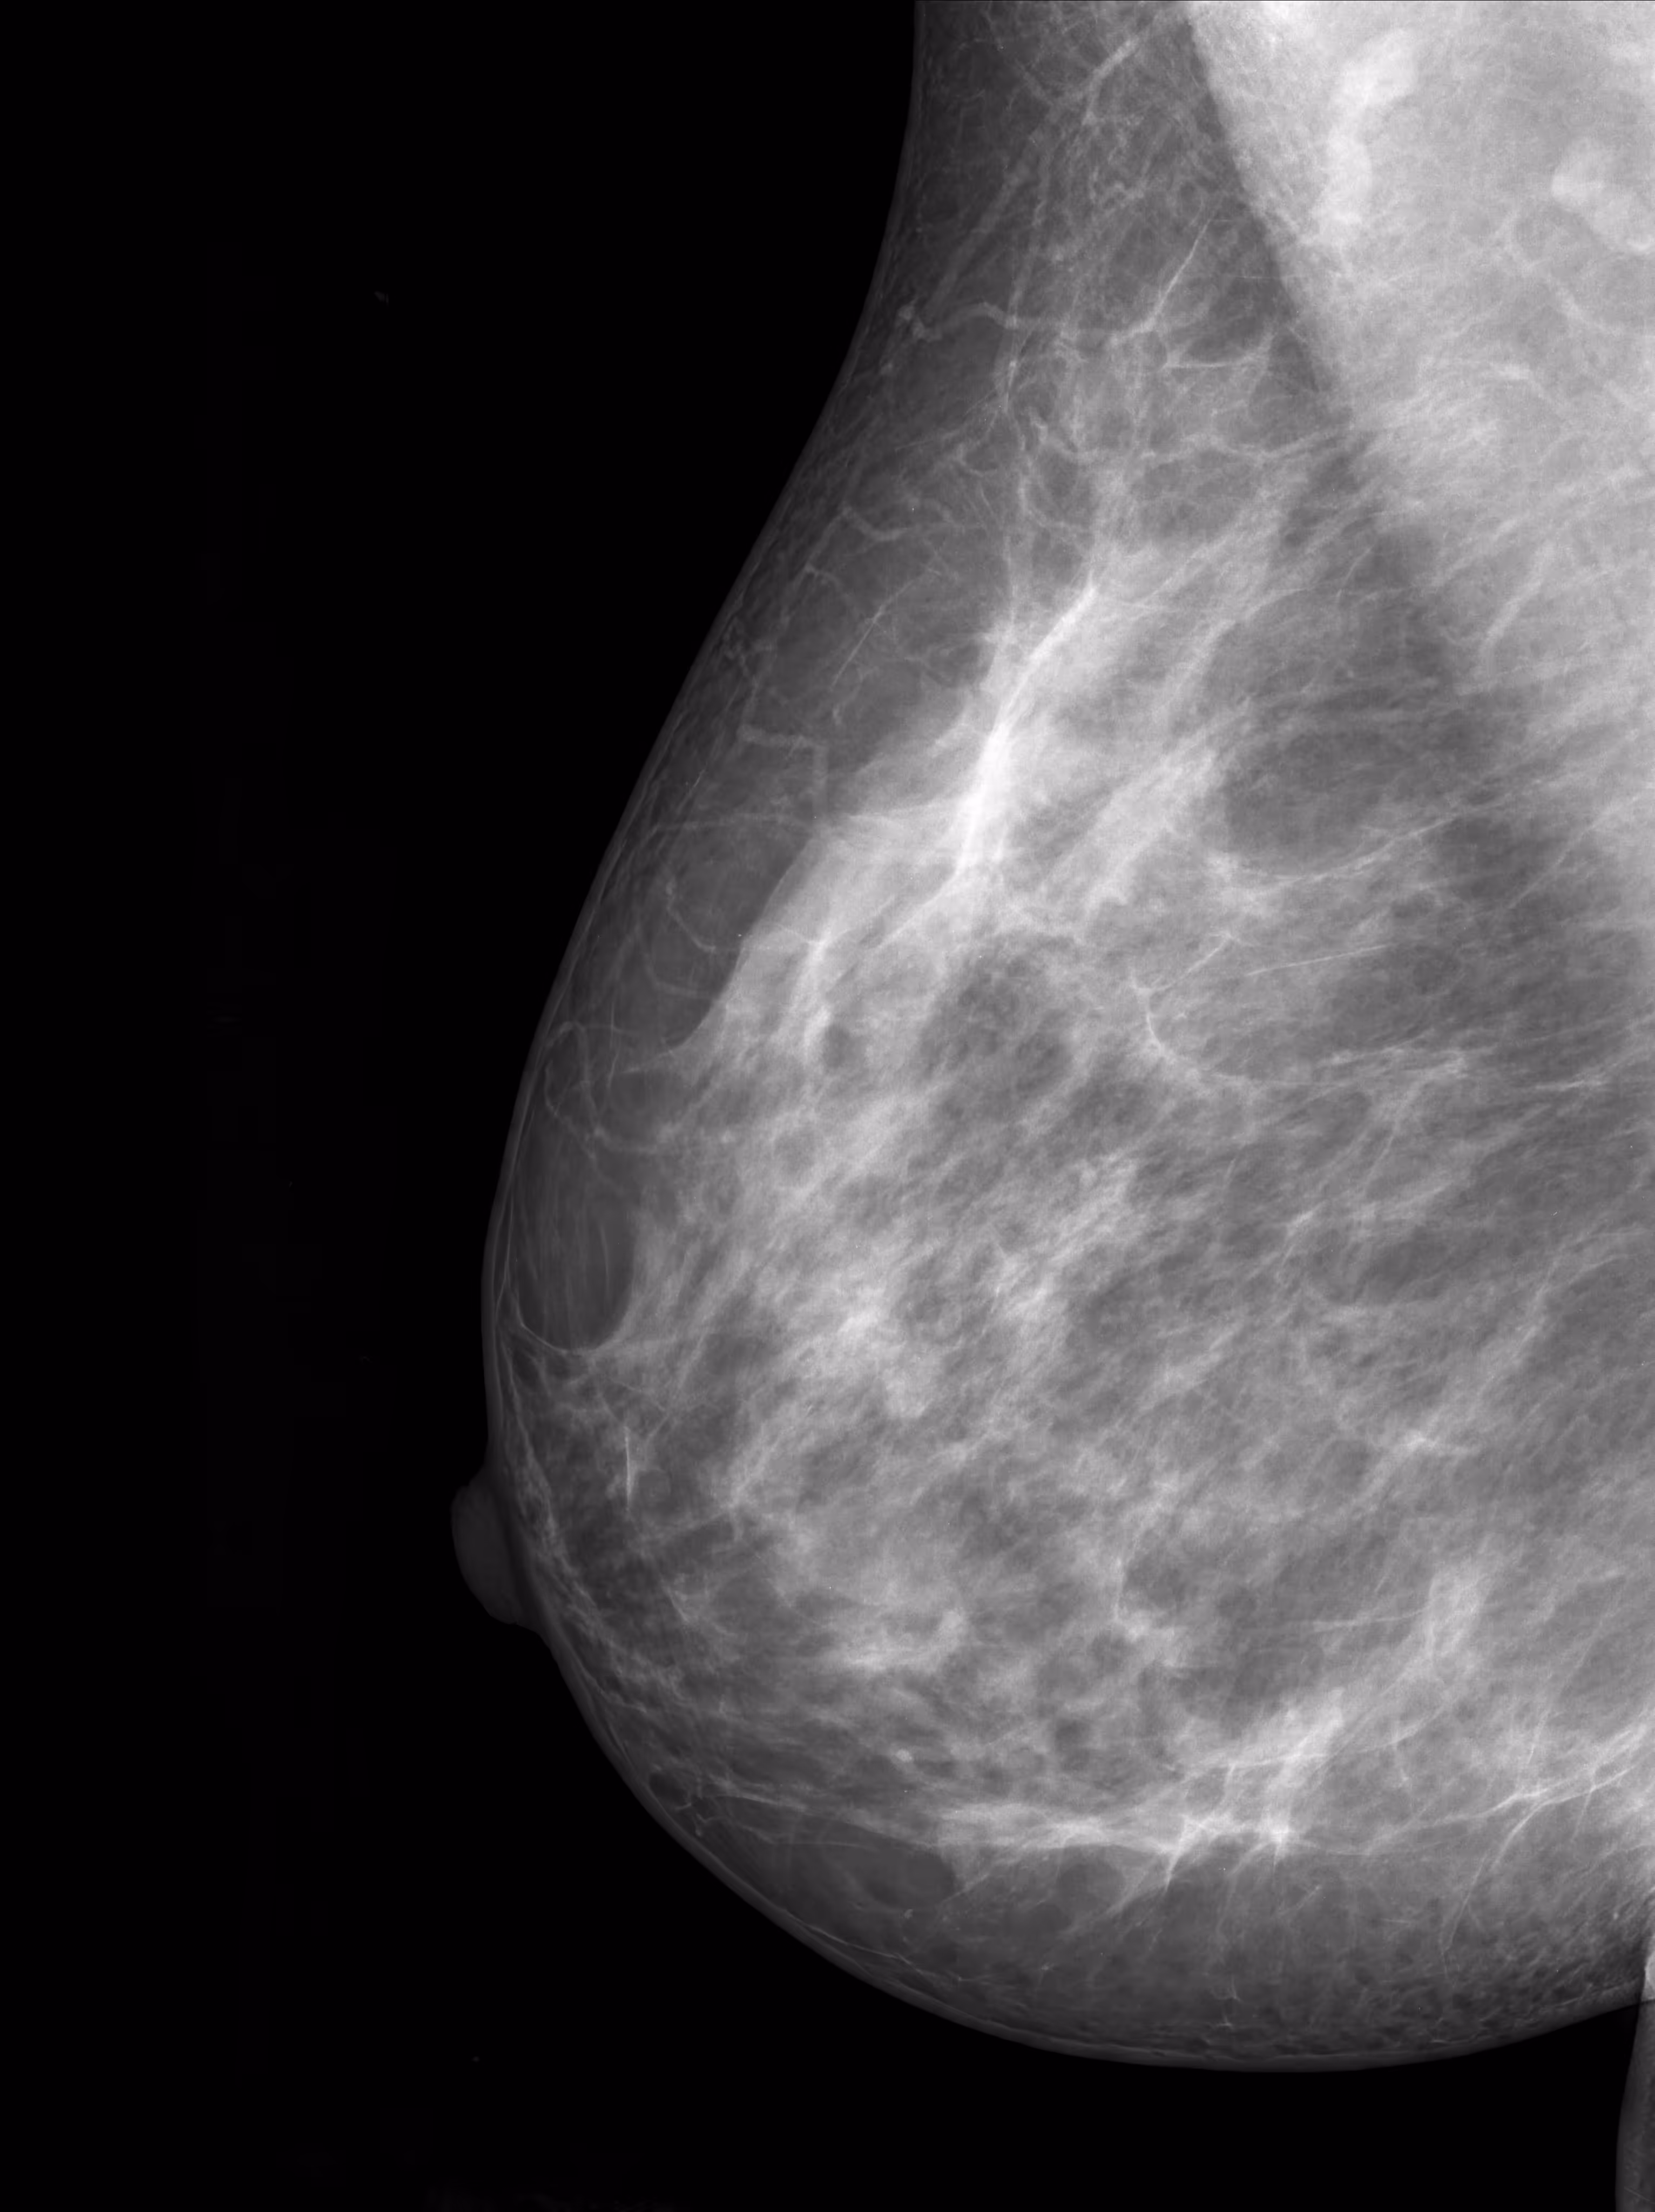

The National Cancer Institute (NCI) categorizes breast density into four levels, ranging from almost entirely fatty to extremely dense. Radiologists determine breast density by reviewing a mammogram. If your breasts fall into the "heterogeneously dense" or "extremely dense" categories, your healthcare provider may discuss additional screening options with you.

Dense breast tissue appears white on a mammogram, which can make it more difficult to detect breast cancer, especially in its early stages. According to the NCI, mammograms may miss about 50% of cancers in extremely dense breasts. This is why women with dense breasts may benefit from additional imaging.